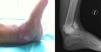

Caso clínicoPaciente mujer de 67 años de edad, diabética con polineuropatía periférica y nefropatía (insuficiencia renal crónica en diálisis) que ingresa en nuestro centro tras sufrir caída accidental con resultado de fractura luxación bimaleolar abierta grado i de tobillo izquierdo (herida de 1cm en cara medial). De urgencia se procede a instaurar la profilaxis antibiótica y al lavado quirúrgico adecuados, tratándose mediante osteosíntesis con placa tercio de caña en maléolo peroneal, tornillo de esponjosa de rosca distal en maléolo tibial y fijación tibioperonea mediante un tornillo, con buen resultado postoperatorio. Tras correcta cicatrización de la herida medial y ausencia de complicaciones, se permite a las 12 semanas una carga parcial de 20kg con ortesis de marcha. A la semana de la carga, acude al Servicio de Urgencias, refiriendo enrojecimiento del tobillo y deformidad indolora del mismo. La radiología muestra en esta fase una pérdida de reducción con destrucción de la articulación (fig. 1). Con la sospecha de infección profunda vs. artropatía de Charcot, se realiza biopsia percutánea con resultado positivo en 4 muestras para S. aureus. Con el diagnóstico de osteomielitis secundaria, se interviene quirúrgicamente, evidenciando desaparición de más del 50% del cartílago astragalino así como fragmentación y signos macroscópicos de osteítis en maléolo peroneal, por lo que se procede a exéresis del maléolo, desbridamiento agresivo e interposición de espaciador de cemento con gentamicina en la articulación tibioastragalina, al que añadimos 2g de vancomicina, según el resultado del antibiograma. Asimismo, se comienza con vancomicina intravenosa ajustada a la función renal durante 6 semanas.